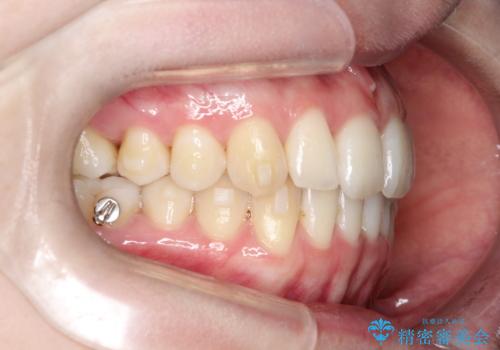

【インビザライン】 前歯の反対咬合を治したい

左下5番は先天性欠損のため乳歯は抜歯しインプラントにて欠損補綴しています。